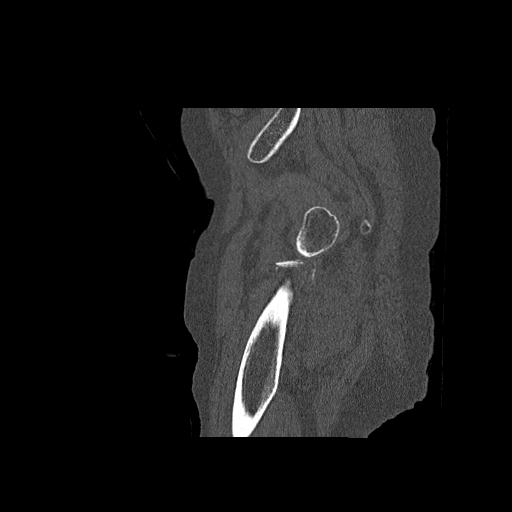

110286 2/17 股関節 2R 74歳女性 右人工骨頭

82084 1/14 1/20 股関節 2R 78歳男性 右人工骨頭

102811 1/13 股関節 2R 1/19 2R 80歳女性 右DHS